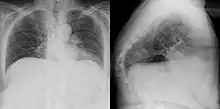

Gibbus deformity

Gibbus deformity is a form of structural kyphosis typically found in the upper lumbar and lower thoracic vertebrae, where one or more adjacent vertebrae become wedged. Gibbus deformity most often develops in young children as a result of spinal tuberculosis and is the result of collapse of vertebral bodies.[1][2][3] This can in turn lead to spinal cord compression causing paraplegia.[4][5]

Gibbus deformity is included in a subset of structural kyphosis that is distinguished by a higher-degree angle in the spinal curve that is specific to these forms of kyphosis. Other conditions within this subset include Pott's disease and Scheuermann kyphosis, but gibbus deformity is marked by an especially sharp angle. Viewed from behind, the resulting hunchback is more easily seen when bending forward.[10] A kyphosis of >70° can be an indication of the need for surgery and these surgeries can be necessary for children as young as two years old, with a reported average of 8 years of age.[9]